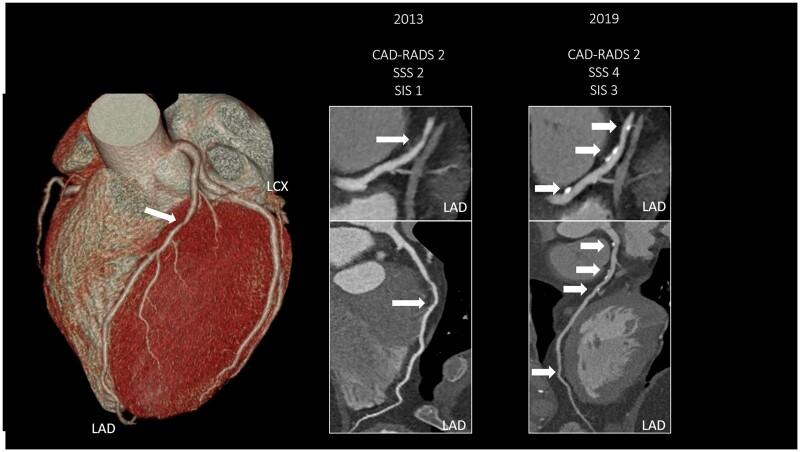

We wished to assess whether different clinical definitions of coronary artery disease (CAD) [segment stenosis and involvement score (SSS, SIS), Coronary Artery Disease-Reporting and Data System (CAD-RADS)] affect which patients are considered to progress and which risk factors affect progression.

We enrolled 115 subsequent patients (60.1 ± 9.6 years, 27% female) who underwent serial coronary computed tomography angiography (CTA) imaging with >1year between the two examinations. CAD was described using SSS, SIS, and CAD-RADS. Linear mixed models were used to investigate the effects of risk factors on the overall amount of CAD and the effect on annual progression rate of different definitions. Coronary plaque burdens were SSS 4.63 ± 4.06 vs. 5.67 ± 5.10, P < 0.001; SIS 3.43 ± 2.53 vs. 3.89 ± 2.65, P < 0.001; CAD-RADS 0:8.7% vs. 0.0% 1:44.3% vs. 40.9%, 2:34.8% vs. 40.9%, 3:7.0% vs. 9.6% 4:3.5% vs. 6.1% 5:1.7% vs. 2.6%, P < 0.001, at baseline and follow-up, respectively. Overall, 53.0%, 29.6%, and 28.7% of patients progressed over time based on SSS, SIS, and CAD-RADS, respectively. Of the patients who progressed based on SSS, only 54% showed changes in CAD-RADS. Smoking and diabetes increased the annual progression rate of SSS by 0.37/year and 0.38/year, respectively (both P < 0.05). Furthermore, each year increase in age raised SSS by 0.12 [confidence interval (CI) 0.05-0.20, P = 0.001] and SIS 0.10 (CI 0.06-0.15, P < 0.001), while female sex was associated with 2.86 lower SSS (CI -4.52 to -1.20, P < 0.001) and 1.68 SIS values (CI -2.65 to -0.77, P = 0.001).

CONCLUSION

CAD-RADS could not capture the progression of CAD in almost half of patients with serial CTA. Differences in CAD definitions may lead to significant differences in patients who are considered to progress, and which risk factors are considered to influence progression.

我们希望评估不同的冠状动脉疾病(CAD)临床定义[节段狭窄和受累评分(SSS、SIS)、冠状动脉疾病报告和数据系统(CAD-RADS)]是否会影响哪些患者被认为会进展,以及哪些危险因素会影响进展。

我们招募了 115 名连续接受冠状动脉计算机断层扫描血管造影(CTA)成像的后续患者(60.1±9.6 岁,27%为女性),两次检查之间间隔>1 年。使用 SSS、SIS 和 CAD-RADS 描述 CAD。线性混合模型用于研究危险因素对总体 CAD 量的影响以及不同定义对年度进展率的影响。冠状动脉斑块负担为 SSS 4.63±4.06 比 5.67±5.10,P<0.001;SIS 3.43±2.53 比 3.89±2.65,P<0.001;CAD-RADS 0:8.7%比 0.0%,1:44.3%比 40.9%,2:34.8%比 40.9%,3:7.0%比 9.6%,4:3.5%比 6.1%,5:1.7%比 2.6%,P<0.001,分别在基线和随访时。总体而言,基于 SSS、SIS 和 CAD-RADS,分别有 53.0%、29.6%和 28.7%的患者随时间进展。基于 SSS 进展的患者中,只有 54%的患者 CAD-RADS 发生变化。吸烟和糖尿病使 SSS 的年度进展率分别增加了 0.37/年和 0.38/年(均 P<0.05)。此外,年龄每年增加 0.12[置信区间(CI)0.05-0.20,P=0.001]和 SIS 0.10(CI 0.06-0.15,P<0.001),而女性与 SSS 降低 2.86[CI-4.52 至-1.20,P<0.001]和 SIS 降低 1.68 有关[CI-2.65 至-0.77,P=0.001]。

结论

CAD-RADS 无法捕捉到连续 CTA 中近一半 CAD 患者的进展。CAD 定义的差异可能导致被认为会进展的患者以及被认为会影响进展的危险因素存在显著差异。